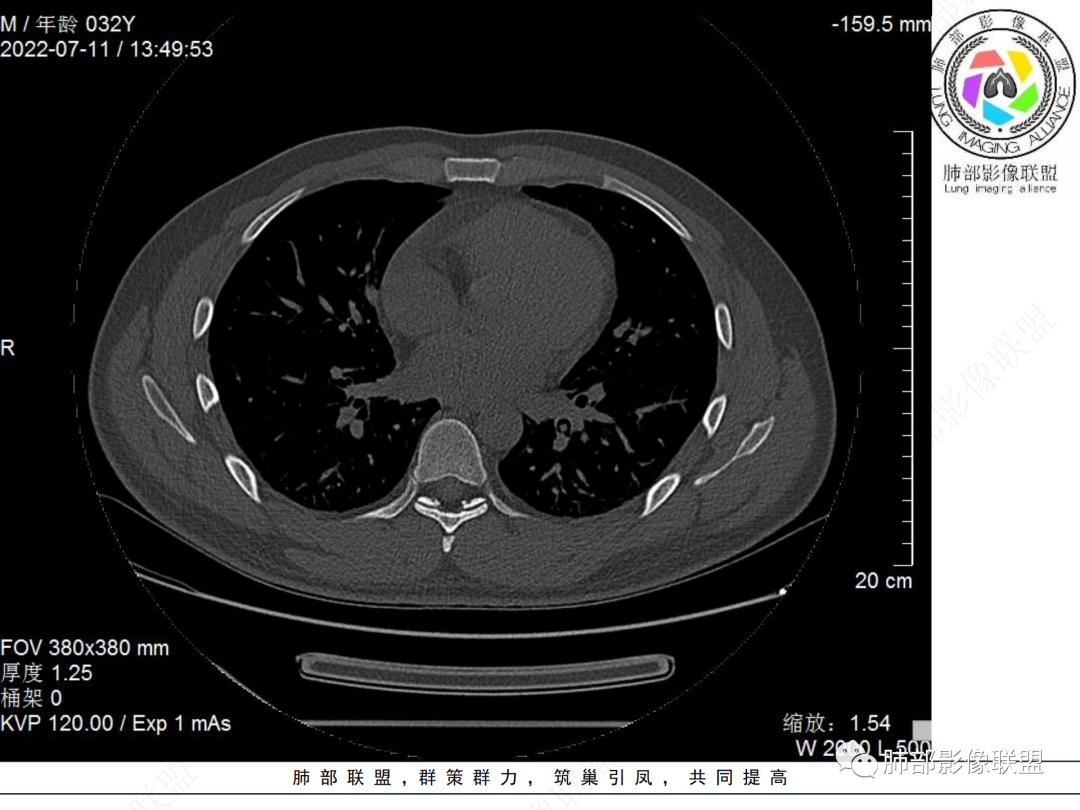

左肺下叶后基底段开口处结节,边缘光滑清楚,没有增强扫描,年轻男性患者痰血三天,考虑1.良性病变:腺瘤、错构瘤、平滑肌瘤

2.恶性:类癌、粘液表皮样癌。

左肺下叶后基底段开口处腔内见壁结节,花生米样,宽基底,补充增强及矢状位重建,确定我无向壁外突破浸润生长,另见强化的特点,临床触之易出血,类Ca可能性大。

年轻男性,咳血,左肺下叶后基底段支气管腔内结节,边缘光滑,首先考虑青年三件套,类癌大于粘液表皮样癌,支气管镜质软,触之易出血,鉴别血管瘤,平滑肌瘤

左肺下叶后基底段开口部结节,密度较均匀一致,边缘较光整,目测密度偏低,支气管镜示:质软、触之易出血,考虑恶性,类癌。

IMT常表现为边缘清晰的周围型结节或肿块,一般体积相对较大。大约10%-20%发生于支气管及气管腔内,表现为中央型病变,一般为单发。IMT胸部CT显示90%为单发结节或肿块。

IMT的影像表现缺乏特异性。部分肿块表现为桃尖征和边缘平直征,界限可清晰有分叶状轮廓,也可界限模糊具有粗长毛刺。肺IMT的CT表现特征与病理具有相关性,可伴有囊变、局灶性钙化、肺实变和空洞样表现。CT增强扫描呈多样性,强化形态和CT值增加幅度呈多样性。粘液血管型增强CT实性成分呈明显花环样强化,静脉期强化进一步增高,此与毛细血管增生与血管管壁通透性增加有关。囊性低密度无强化区镜下为黏液样变形、炎性渗出或坏死。梭形细胞密集型增强扫描呈渐进性延迟强化特点,但强化程度弱于黏液血管型。少细胞纤维型增强扫描实性成分强化不明显或呈轻中度强化。PET/CT上IMT具有很高的SUV值。IMT高摄取的可能原因可能与激烈炎症导致的代谢活动增加有关,这使得IMT与其他恶性肿瘤难以区分。